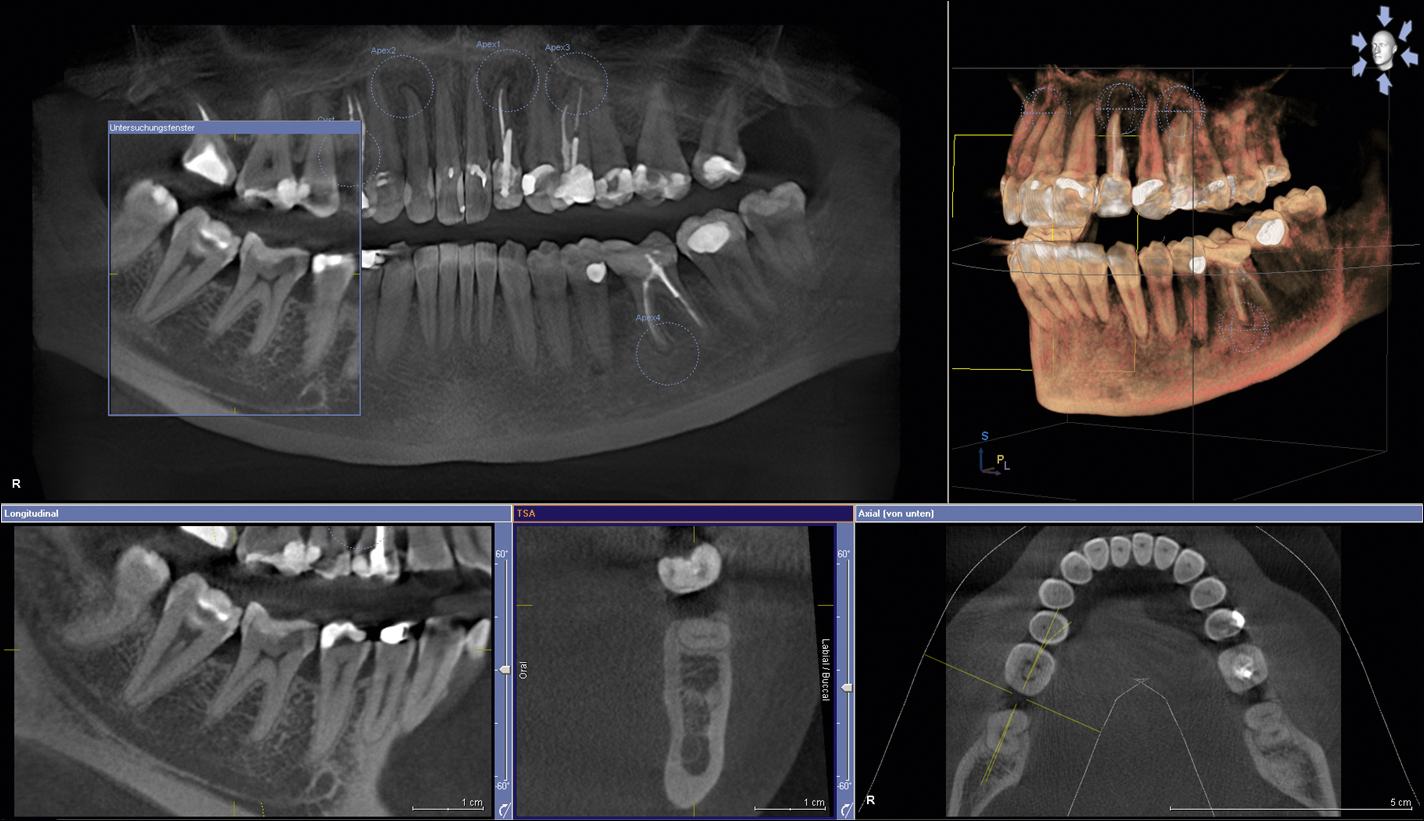

Debido a que trabajamos con la más avanzada tecnologia todas las radiografias digitales pueden ser entregadas/enviadas: Impresas en peliculas radiográficas con formato médico de alto contraste, CD y/o correo electrónico.